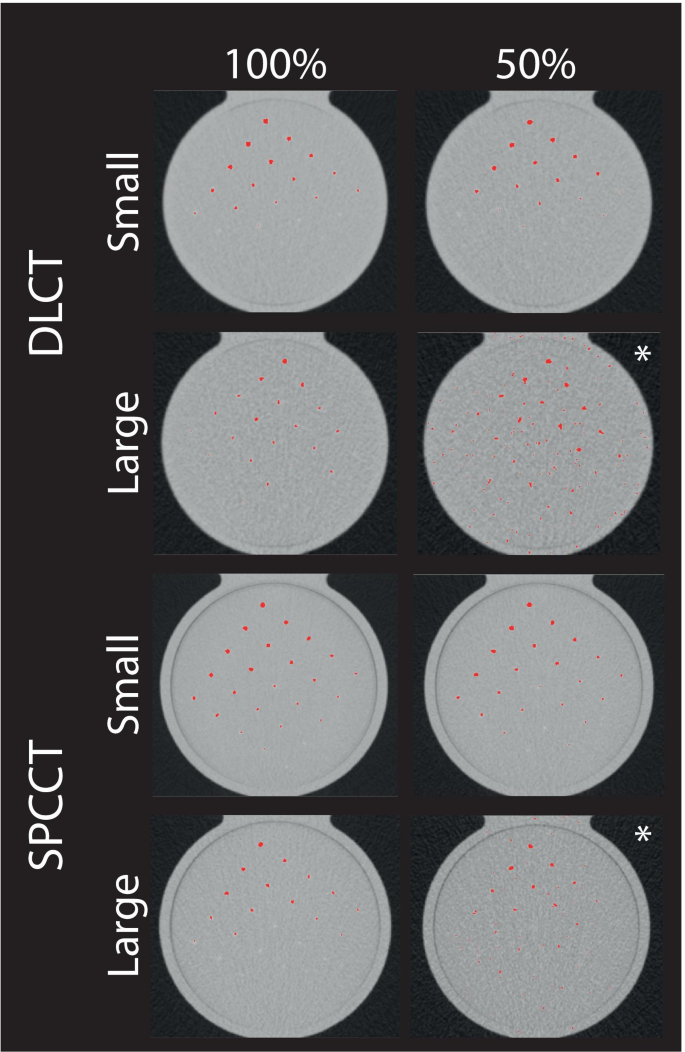

The promise of spectral photoncounting CT (SPCCT) As a firstline diagnostic tool used in everything from cancer and cardiovascular disease toE potential to increase image quality and reduce artifacts due to its advanced detector technology Our study aimed to verify the technical and clinical potential of a novel SPCCT prototype using an ISR phantom setup Materials and Methods Soft plaquelike restenosis (45 HU;

Spcctv 2022-SPCCT is able to distinguish between two contrast agents referred to as multicolor imaging because, when measuring in three or more energy regimes, it can detect and quantify elements with a Kedge in the diagnostic energy range Based on this capability, we tested the feasibility of a dualcontrast multiphase liver imaging protocol via thePr Philippe DOUEK is the SPCCT coordinator He is Chairman of a consortium of 10 Departments of Radiology and Nuclear Medicine in Lyon Hospital (HCL), France, including 60 physicians and researchers, and 600 paramedical employees;